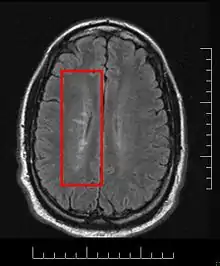

Multiple sclerosis is considered a disease of the white matter because normally lesions appear in this area, but it is also possible to find some of them in the grey matter.[30]

Using high field MRI system, with several variants several areas show lesions, and can be spacially classified in infratentorial, callosal, juxtacortical, periventricular, and other white matter areas.[31] Other authors simplify this in three regions: intracortical, mixed gray-white matter, and juxtacortical.[32] Others classify them as hippocampal, cortical, and WM lesions,[33] and finally, others give seven areas: intracortical, mixed white matter-gray matter, juxtacortical, deep gray matter, periventricular white matter, deep white matter, and infratentorial lesions.[34] The distribution of the lesions could be linked to the clinical evolution[35]

Due to the distribution of the lesions, since 1916 they are also known as Dawson's fingers.[40] They appear around the brain blood vessels.

Most MS lesions are isointense to white matter (they appear bright) on T1-weighted MRI, but some are "hypointense" (lower intensity). These are called "black holes" (BH). They appear specially in the supratentorial region of the brain.

When BH's appear, around half of them revert in a month. This is considered a sign of remyelination. When they remain, this is regarded as a sign of permanent demyelination and axonal loss. This has been shown on post-mortem autopsies.[96]